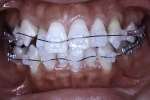

| 初診時

| 治療中